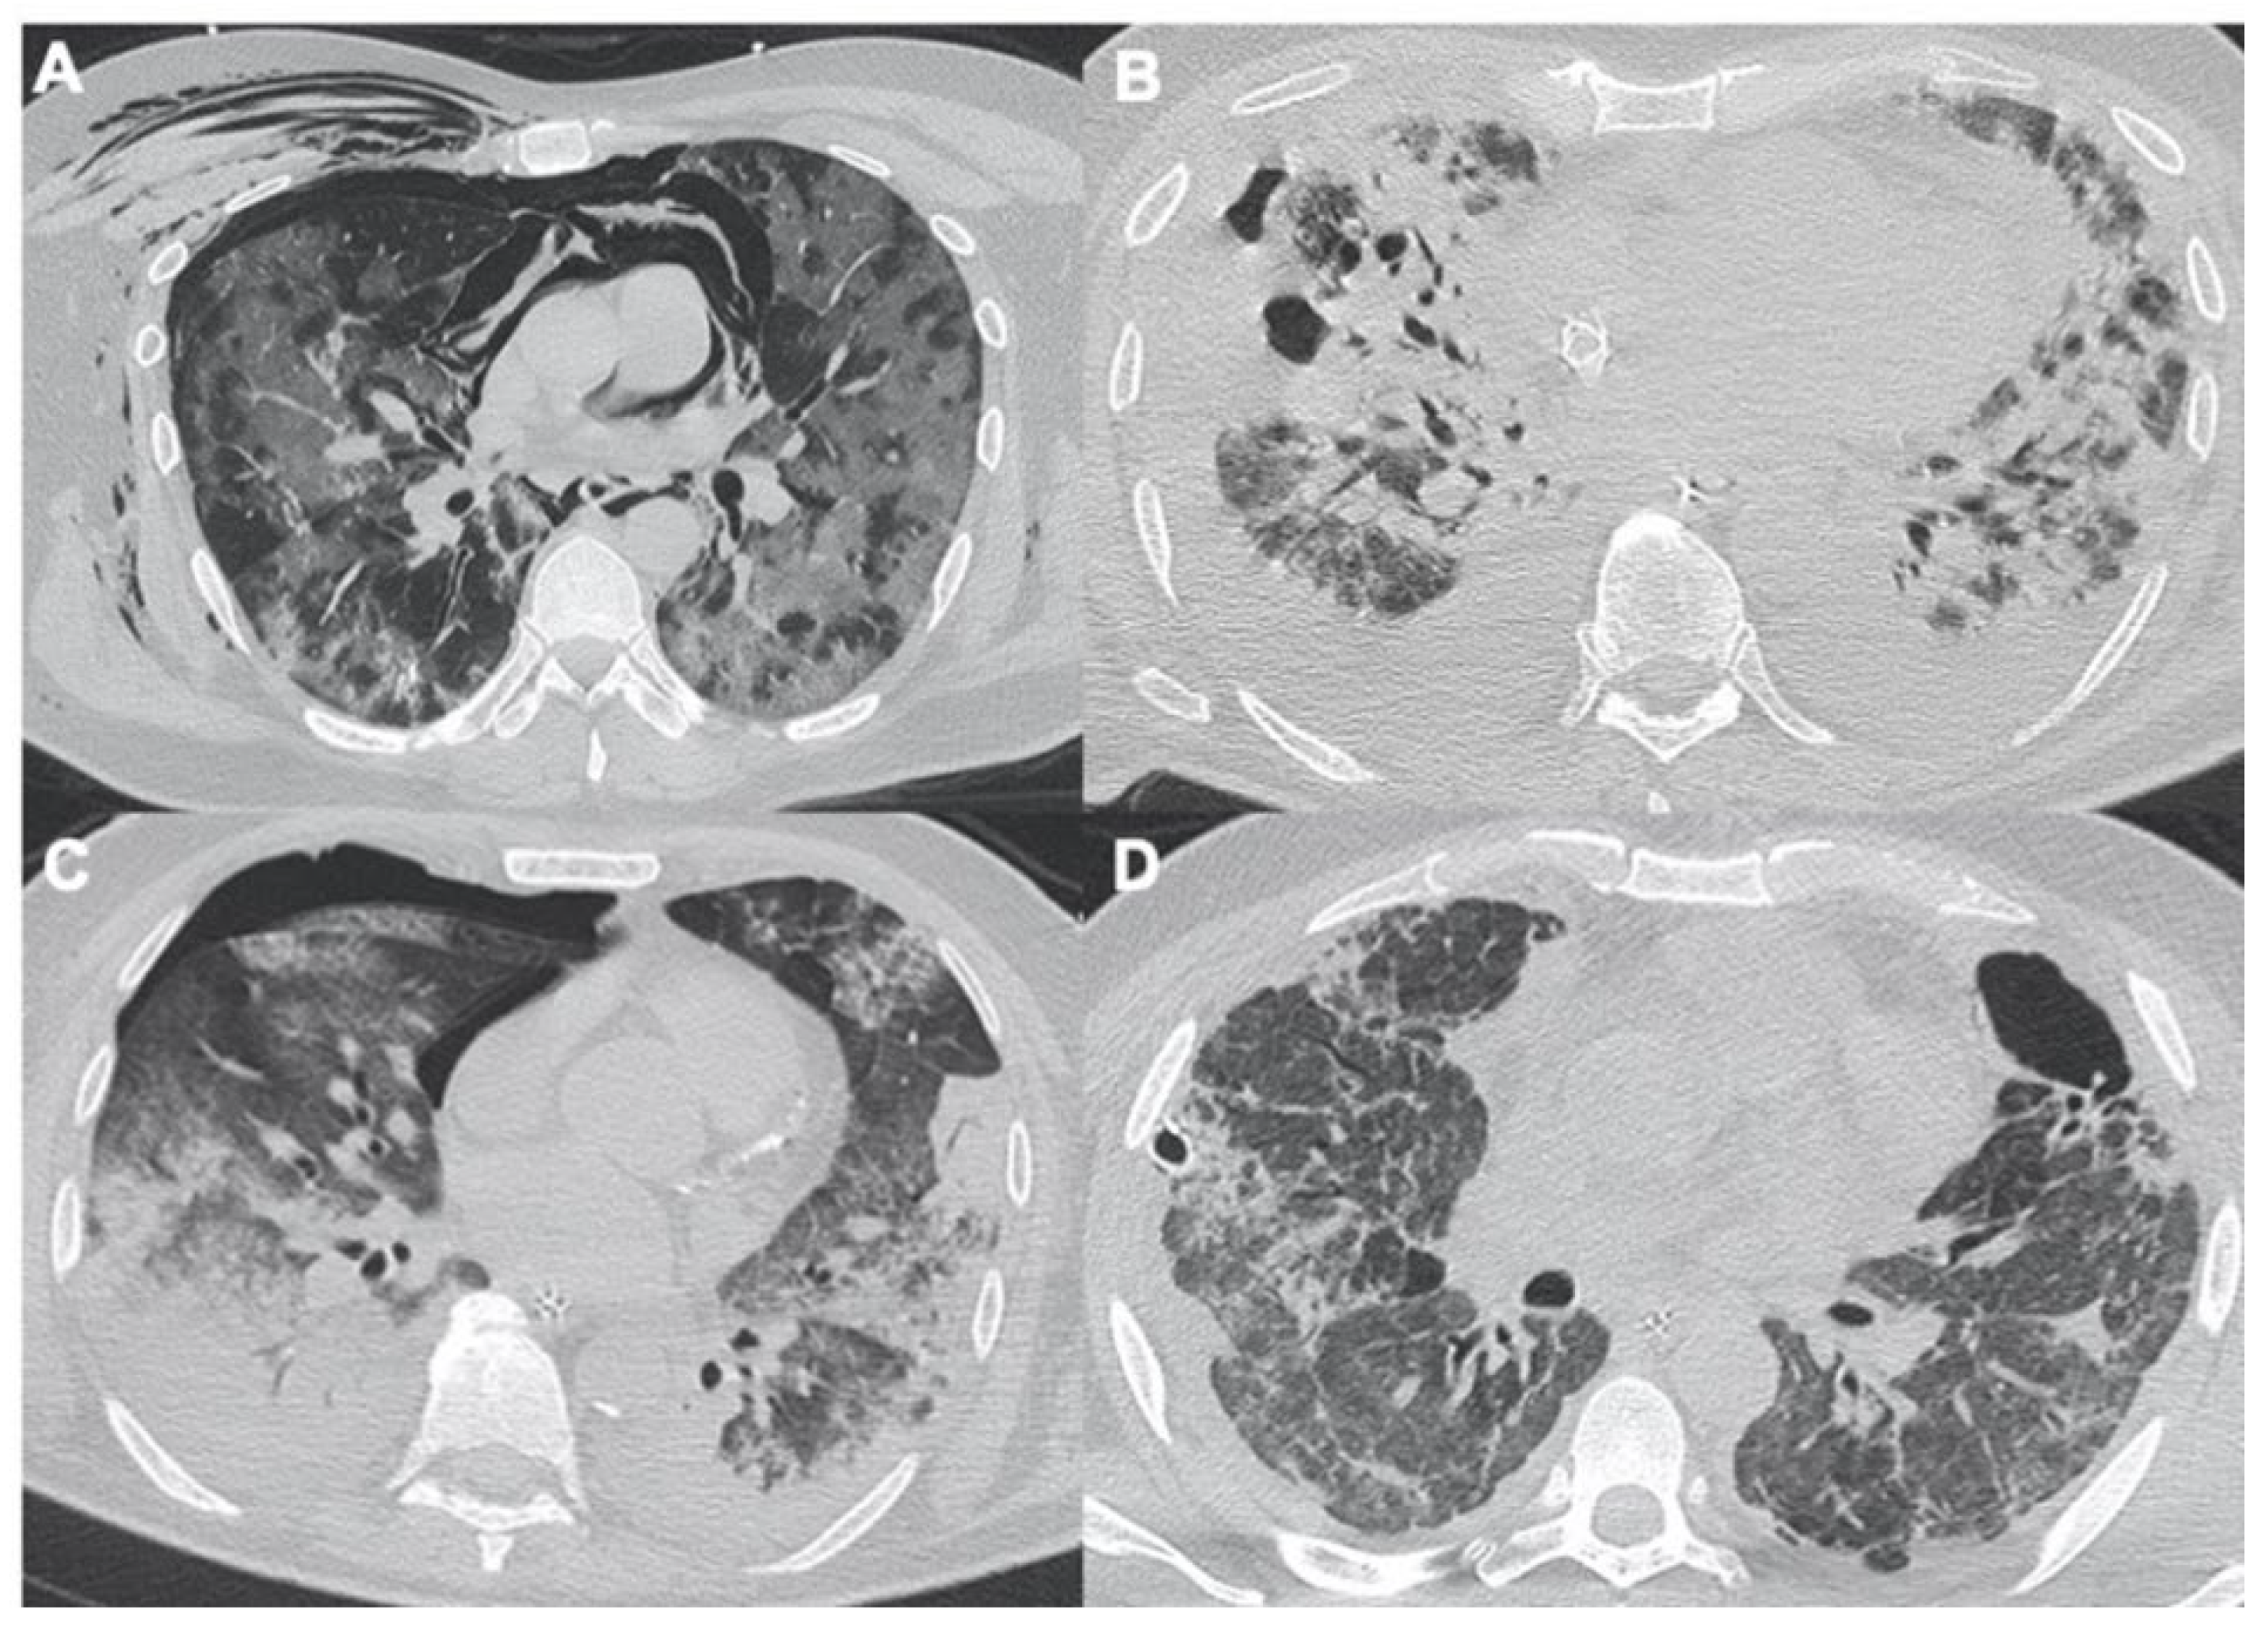

2.1. Pneumonia

2.2. Acute Respiratory Disease Syndrome